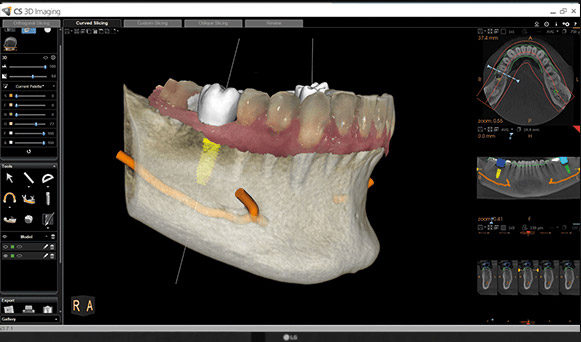

The information is provided to the dental practitioner in Dicom™ format which is industry standard and includes viewing software to manipulate and calculate measurements required. This Dicom™ format may also be converted by proprietary software packages such as Simplant™. This is not carried out unless requested.

DSS use Carestream 8200 3D by Visualise 360 providing digital technology operating the “variable field of view” process which allows the dose of radiation to be considerably reduced. A proven and versatile CBCT system featuring an extended field of view that is ideal for practitioners who want to expand their treatment capabilities. Powered by premium imaging technologies and software, the CS 8200 3D delivers superb image quality in all modalities.

Versatile 2D/3D system ideal for expanding treatment capabilities

Outstanding 2D/3D images thanks

to the latest premium technology

High-resolution 3D images

with limited artifacts and noise

State-of-the-art 2D/3D software

for easy image review